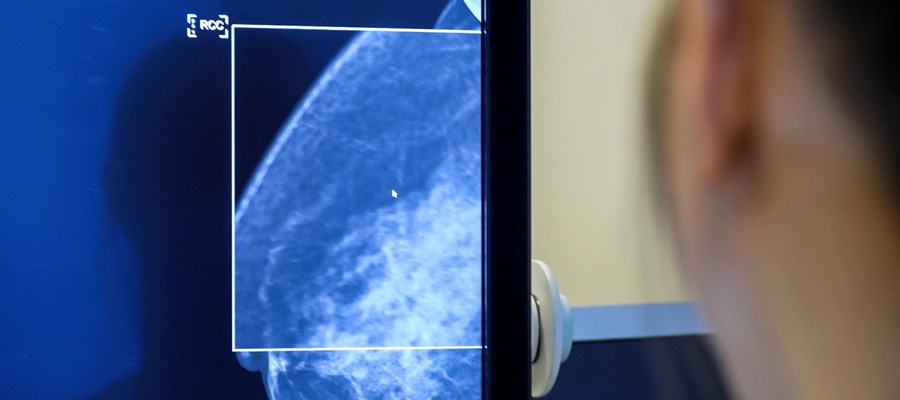

I Sverige kallas alla kvinnor mellan 40-74 år till regelbunden screening med hjälp av mammografi, för att upptäcka bröstcancer. Genom mammografi kan man hitta en bröstcancer i ett tidigt skede och därmed öka chansen för lindrigare behandling och överlevnad. Ungefär 2 av 3 bröstcancerfall upptäcks på det sättet.

— Det som har hänt nu är fantastiskt spännande, att man bara genom att AI analyserar själva mammografibilden bättre kan förutsäga risken än med de klassiska kliniska modellerna. Det vore ett enkelt sätt att börja individuella screening utifrån den enskilda kvinnans risk, säger Sophia Zachrisson.